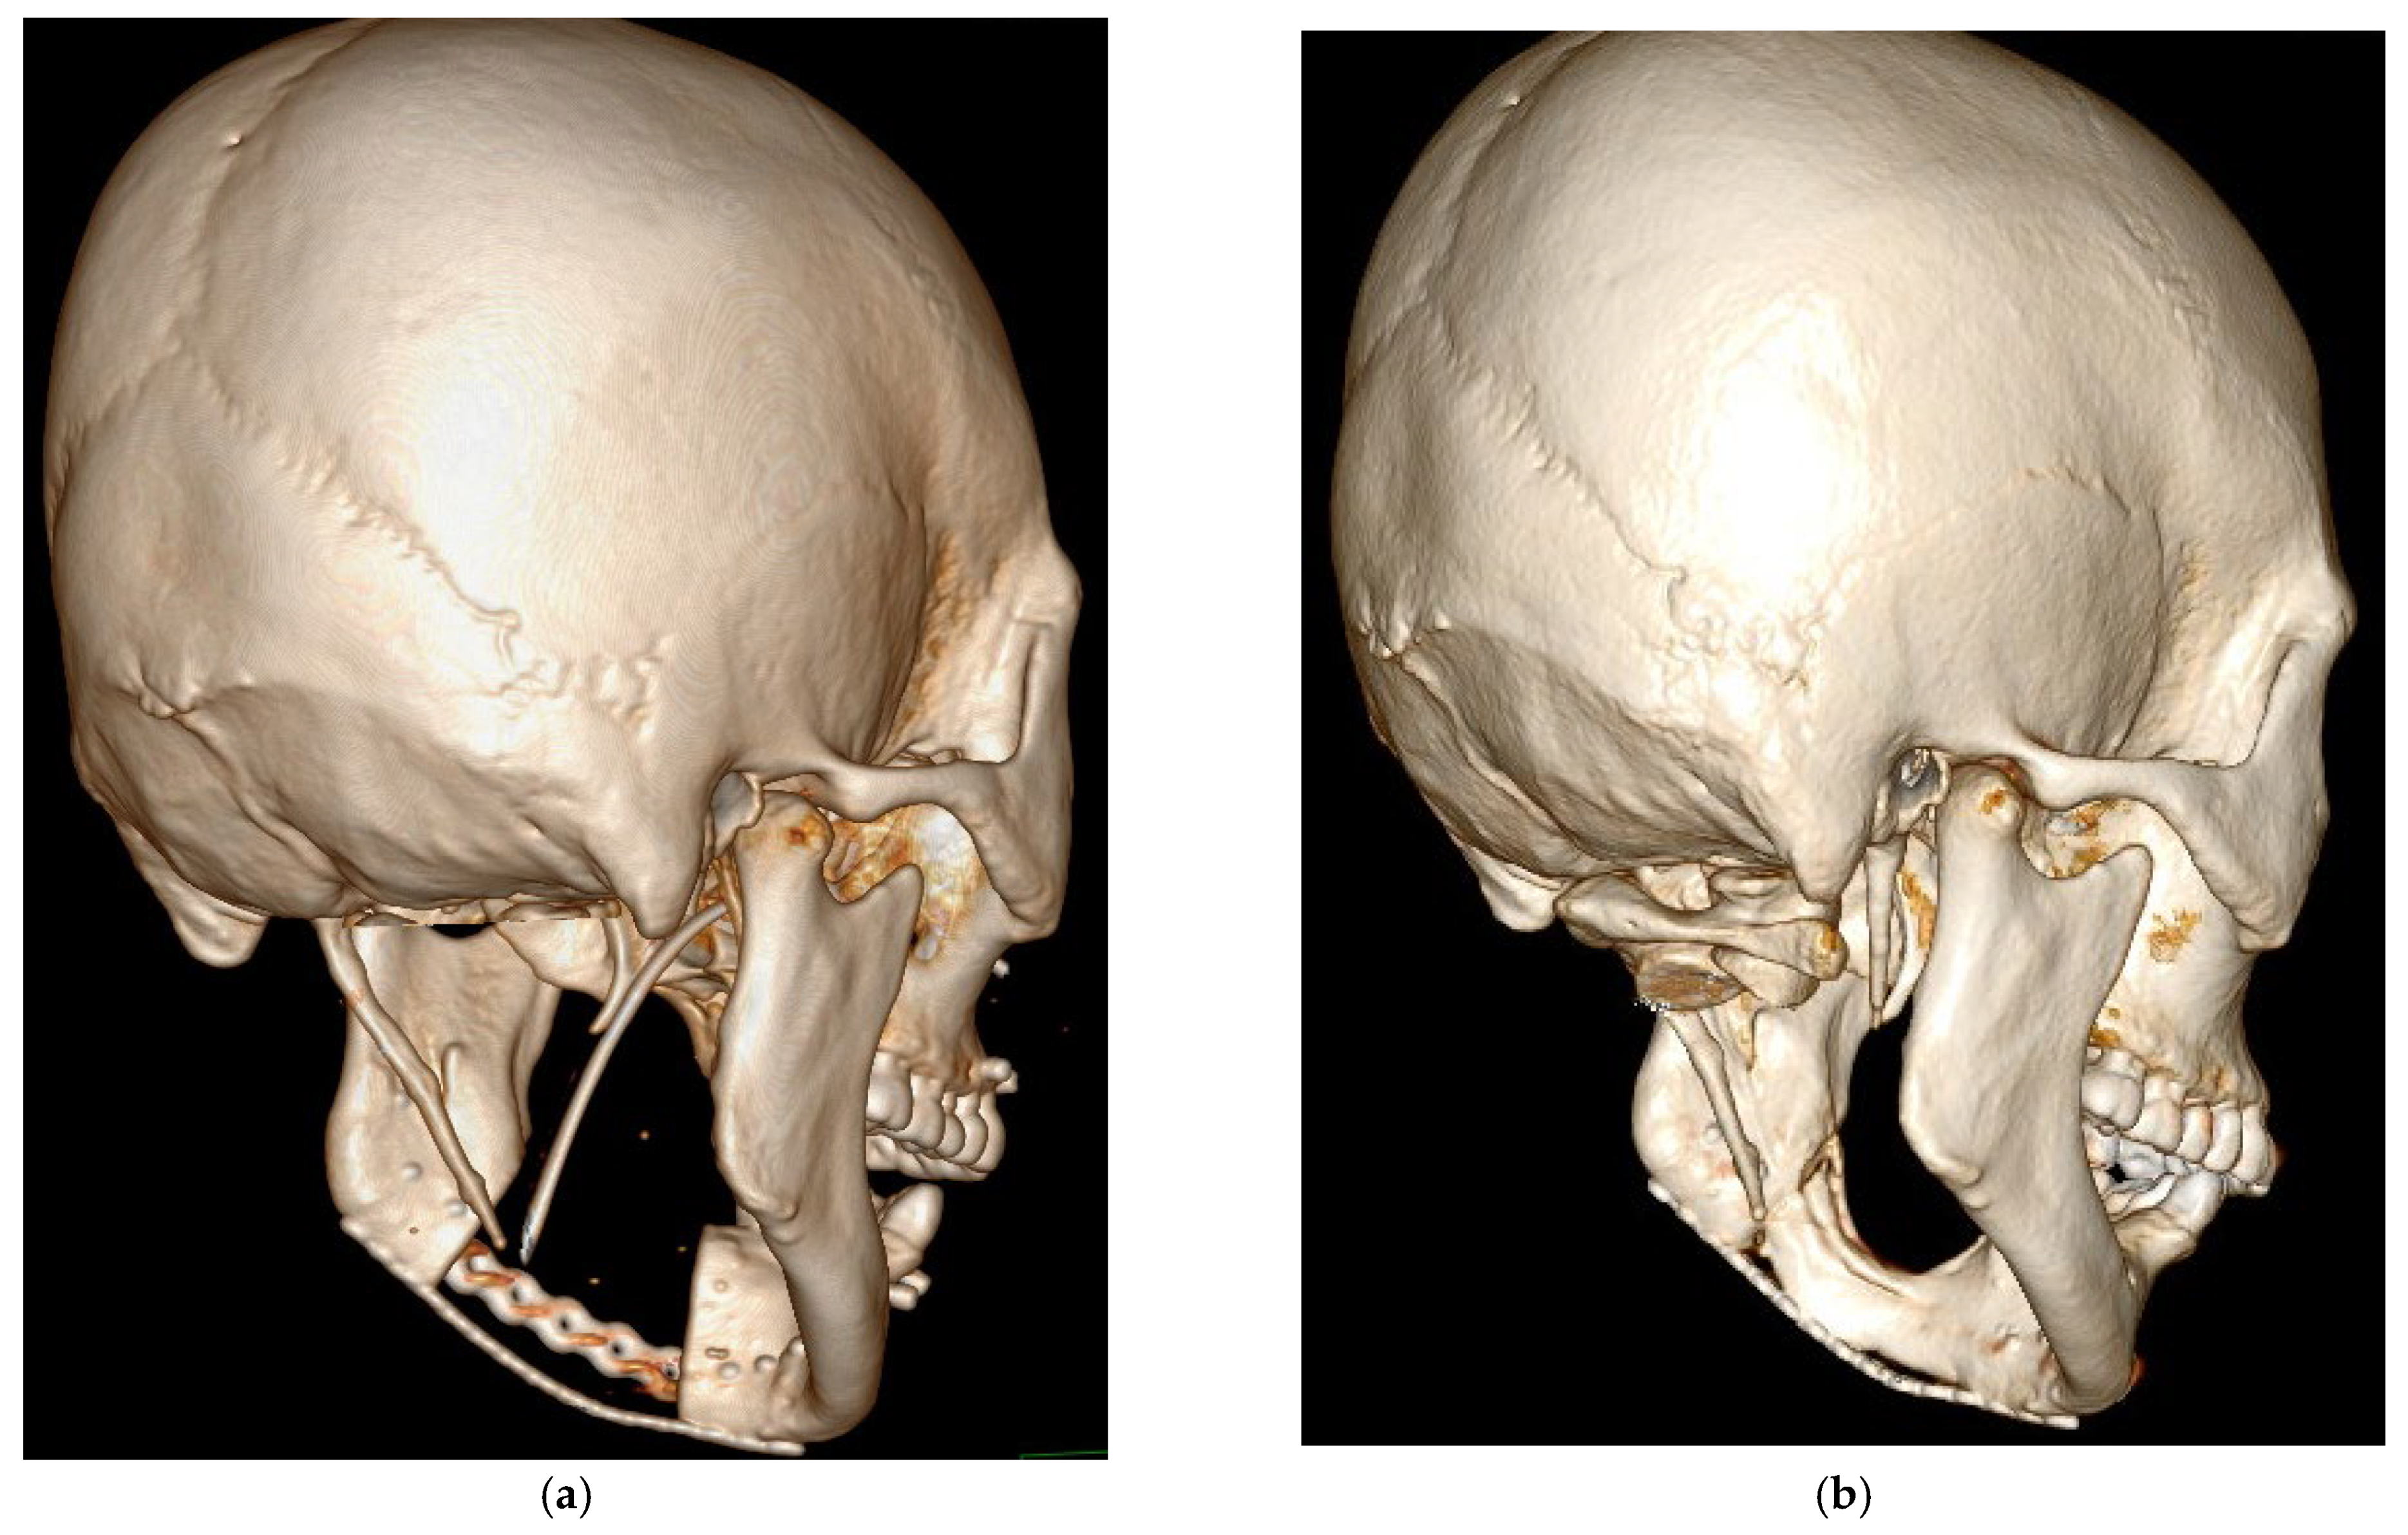

Spontaneous Osteogenic Potential of Periosteum after Segmental Mandibulectomy in Patients with Medication-Related Osteonecrosis of the Jaw (MRONJ): A Retrospective Study of 14 Cases

3. Results